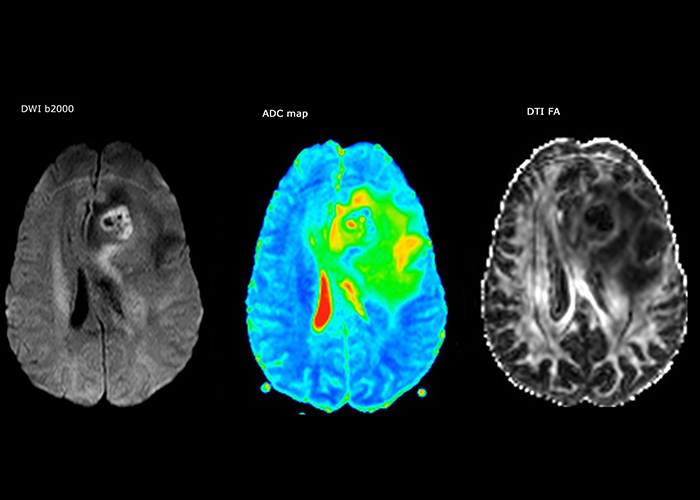

The first challenge in MRI of stroke is speed. The patient typically arrives from an ambulance in the MRI preparation room and the installation is done on a separate dock outside the scanner room. “The venous access is placed during the neurological examination. If the delay from the first symptoms allows the patient to receive thrombolysis we do a very fast examination that typically lasts about 11 minutes including the pre-scans. In the case of transient ischemic stroke we usually add ASL perfusion because in some symptoms with negative diffusion, ASL sometimes indicates a vascular origin.”

“Ingenia provides great flexibility in the parameters setting. We can tune a sequence the way we want,” says Dr. Savatovsky. “For example, in a stroke exam we use a FLAIR sequence of about two minutes instead of the four-minute FLAIR we use for MS. The diffusion is 30 seconds, the T2*-weighted scan is 30 seconds, the angiography scan time is less than one minute. Ingenia is a great scanner in that situation; even with these fast sequences we can achieve good images with good SNR. When the first sequence tells us that it’s not an ischemic stroke but a hemorrhagic stroke, we may switch to a time-resolved angiography to look for vascular malformations and venous thrombosis.

“Every center is different, but for me the ideal protocol for stroke includes diffusion weighted imaging, FLAIR, and fast susceptibility imaging,” says Dr. Savatovsky. “Our fast susceptibility weighted imaging takes 50 seconds, so it’s as fast as T2*-weighted imaging. It visualizes hemorrhage but also the clots. We also do 3D MR angiography that provides information on cervical and brain vessels. If the patient does not need immediate treatment, or if additional information is needed to decide on treatment, we might also add perfusion imaging and post-contrast T1-weighted imaging.”